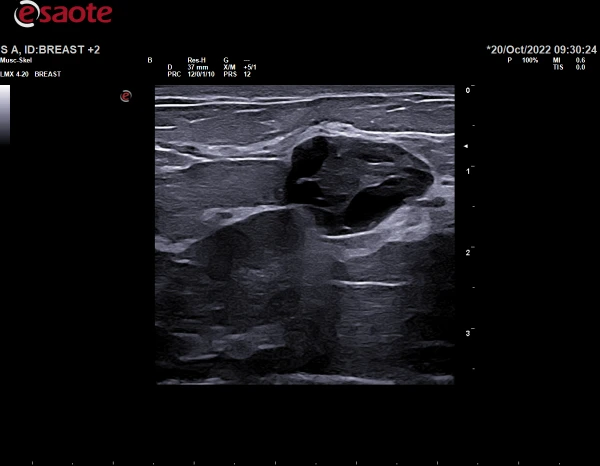

Qalqonsimon bez va sut bezlarida shubhali joylarni avtomatik konturlash;

HD Single Crystal texnologiyasi sirt konstruksiyalarini vizuallashtirishda haqiqiy texnologik yutuqdir. ClearWave arxitekturasining LMX 4-20 ultratovush transduserida 25 MGts gacha bo'lgan HD Single Crystal bilan kombinatsiyasi chuqur tasvir sifatini saqlab qolgan holda tasvirning o'ta tiniqligi va tafsilotlarini ta'minlaydi.